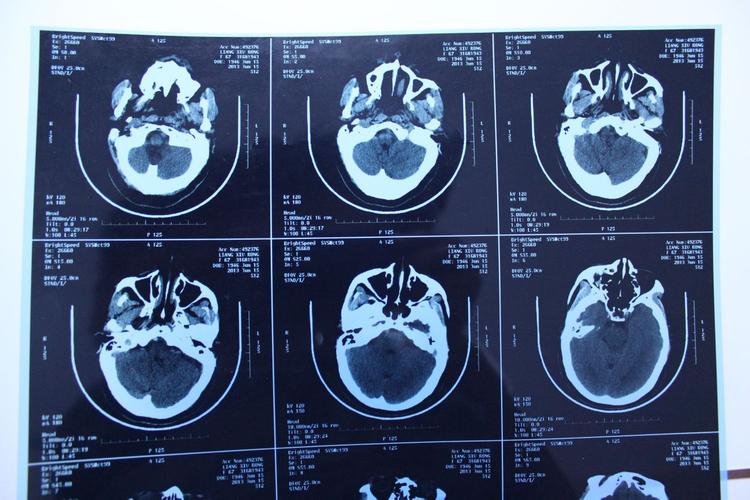

如何从图片上定位脑梗?

医生会通过MRI上的定位图来确定梗死的位置。

(图片来源网络,侵删)

- 横断面:像切面包一样,从头顶到脚底一层一层扫描,这是最常用的观察平面。

- 冠状面:像从正面给大脑拍一张X光片。

- 矢状面:像从侧面给大脑拍一张X光片。

通过这三个平面,医生可以精确地指出梗死灶位于大脑的哪个叶(如额叶、颞叶、顶叶、枕叶)、哪个脑区(如基底节区、丘脑、脑干、小脑),以及具体影响了哪些功能(如运动区、语言区等)。“左侧大脑中动脉供血区急性梗死”,就表明左侧大脑半球的很大一部分区域发生了缺血。